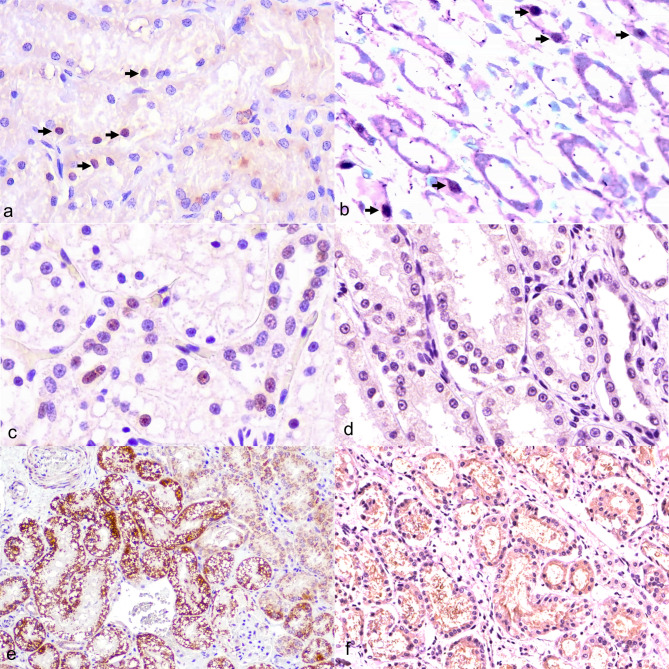

Methods: Kidney tissues from 150 deceased cats with suspected or confirmed chronic kidney disease (CKD) were screened for FeMV using conventional reverse-transcription PCR (cRT-PCR). Positive cases were genotyped and quantified for viral load using reverse-transcription digital PCR (RT-dPCR). A control group of nine FeMV-negative kidneys with CKD was included for comparison. Histological evaluation was conducted using hematoxylin and eosin (H&E), periodic acid-Schiff (PAS), and Masson's trichrome staining. Immunohistochemistry (IHC) and in situ hybridization (ISH) were employed to localize viral antigens and assess expression of apoptotic markers, including cleaved caspase-3 (cCasp3), B-cell lymphoma 2 (BCL-2), and BCL-2-associated X protein (BAX).

Results: FeMV RNA was detected in 6% (9/150) of kidneys, all classified as genotype 1. Histological findings in FeMV-positive cases included eosinophilic intracytoplasmic inclusion bodies, lymphoplasmacytic tubulointerstitial nephritis (TIN) and varying degrees of fibrosis. FeMV antigens were localized in the renal tubular epithelial cells. Statistically, cCasp3 expression (P = 0.005) and interstitial fibrosis (P = 0.040) were significantly higher in FeMV-positive cases than in FeMV-negative controls. No significant differences were observed for TIN, BAX, or BCL-2 expression (P > 0.05). Among FeMV-positive cases, viral load was significantly associated with cCasp3 expression (P = 0.049), but not with TIN, fibrosis, BAX, or BCL-2 expression. Spearman's correlation revealed a strong positive correlation between viral load and cCasp3 expression (ρ = 0.8222, P = 0.007).